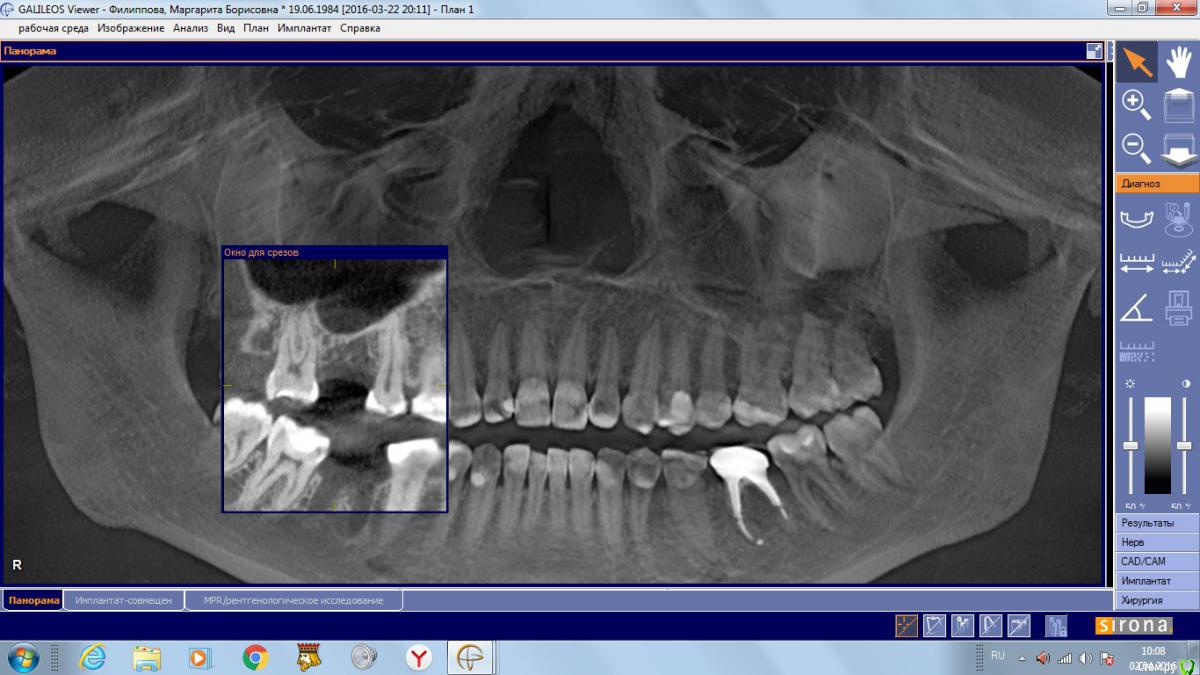

Маргарита19 Опубликовано 2 апреля, 2016 Автор Поделиться Опубликовано 2 апреля, 2016 Спасибо за ответ. Вот такой скрин подойдёт? Ссылка на комментарий

red_butler Опубликовано 2 апреля, 2016 Поделиться Опубликовано 2 апреля, 2016 Спасибо за ответ. Вот такой скрин подойдёт?Не совсем, но похоже можно закрытым синуслифтом обойтись. Скрин области интереса нужен в щечно - небной плоскость, а Вы выкладываете реконструкцию панорамы. 1 Ссылка на комментарий

Маргарита19 Опубликовано 2 апреля, 2016 Автор Поделиться Опубликовано 2 апреля, 2016 Не совсем, но похоже можно закрытым синуслифтом обойтись. Скрин области интереса нужен в щечно - небной плоскость, а Вы выкладываете реконструкцию панорамы.Не могу справиться с компом, перестал показывать 3Д, только панорама и все... Я так понимаю КТ целое от сироны скачивать никто не будет или можно рискнуть и разместить ссылку? Ссылка на комментарий

Маргарита19 Опубликовано 22 августа, 2016 Автор Поделиться Опубликовано 22 августа, 2016 Уважаемые стоматологи, помогите, пожалуйста определиться с выбором импланта и схемы лечения. вопрос идет только о 46 зубе, на синус-лифтинг пока не могу решиться. Посетив несколько клиник, стою перед выбором из 2 вариантов: 1. Имплант Нобель Коникал коннекшн (8 мм), временные коронки, потом циркониевые коронки. Но здесь есть еще нюанс, ортодонт советует установить брекеты на нижнюю челюсть, чтобы выровнять передние зубы, там есть небольшая скученность. Сначала подпилить зубы немного по ширине, а потом приклеить брекеты только на 8 зубов, т.к. клыки смыкаются четко. Пока ТРГ и слепков нет, это предварительный план. Меня никогда не беспокоили нижние зубы в плане кривизны. Но, как я поняла, есть нездоровая стираемость зубов. 2. Хирургический шаблон, подсыпать кость искусственную, и Имплант Биотек Коннект (12мм), потом коронки МК, без временных. Про истираемость зубов ничего не сказали, но я и не спрашивала, если честно. Знакомых или проверенных врачей или клиник нет у меня. Вот пытаюсь понять в чьи руки отдаться. Ибо через пол годика хочу решиться на синус и делать его уже имея опыт общения с докторами. Какая схема на ваш взгляд более логичная и какой имлант лучше поставить? Заранее благодарю. Снимки прикрепляю как смогла сделать с КТ. Ссылка на комментарий